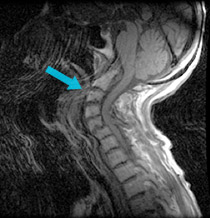

An elderly woman had difficulty walking and swallowing from bony pressure on her spinal cord and brainstem due to arthritic breakdown at the top of her spine (odontoid pannus).

Pre-surgical scan shows bone pressing on the spinal cord and brainstem.